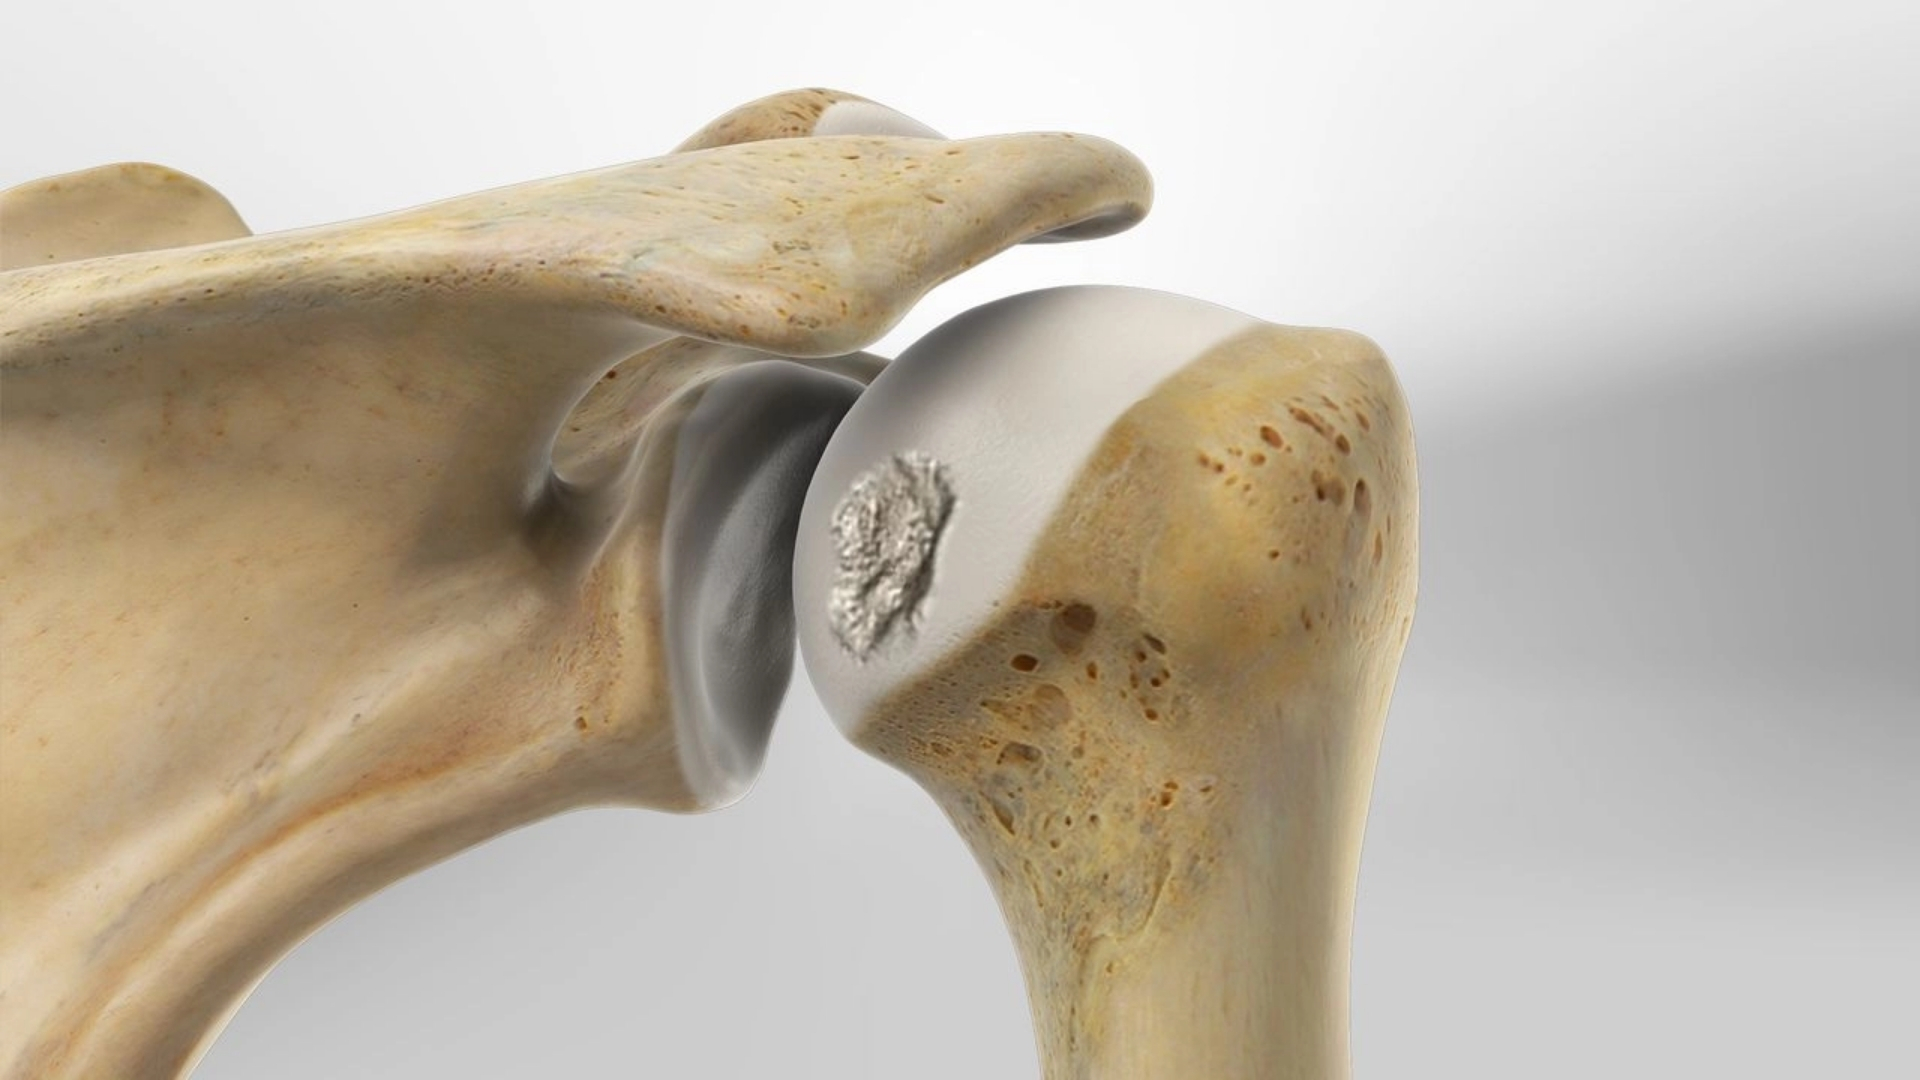

Tổn thương xương (tổn thương Hill-Sachs và khuyết xương ổ chảo)

Khi chỏm xương cánh tay va đập mạnh vào bờ ổ chảo trong lúc trật khớp, có thể gây lõm xương (Hill-Sachs). Đồng thời, phần xương ổ chảo cũng có thể bị mẻ hoặc khuyết. Những tổn thương này làm giảm diện tích tiếp xúc và sự tương đồng của khớp, dẫn đến dễ tái trật khớp vai.